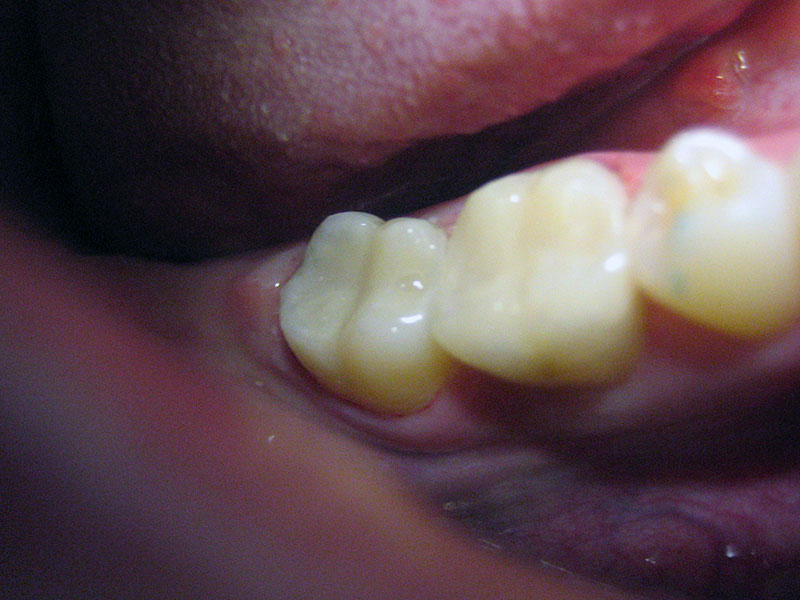

Dječja i preventivna dentalna medicina